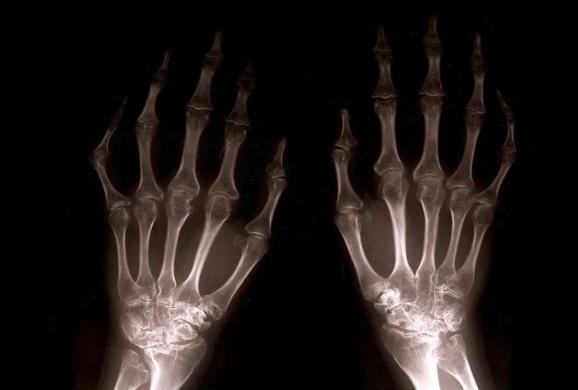

如何判断类风湿关节炎病情稳定不反复?满足这3个条件就是了!

我们知道,类风湿关节炎主要病理改变为滑膜炎,滑膜异常增生是导致关节病变的罪魁祸首,治疗上所有的药物也是在尽最大程度减轻和抑制滑膜增生。

关节症状改善了,炎性指标下降了,滑膜增生相应会减轻,但减轻不代表完全没有增生。

事实上,此时不少患者依然处于滑膜轻度增生状态,只是还没能引起关节症状与炎性指标异常,这也病情再次反复的原因。

临床上,一般会通过关节超声、核磁等检查方法去查看滑膜增生情况,并根据滑膜增生程度制定下一步治疗方案。

但就目前医疗水平与治疗现状而言,绝大多数类风湿关节炎患者达到影像学改善仍较为困难。